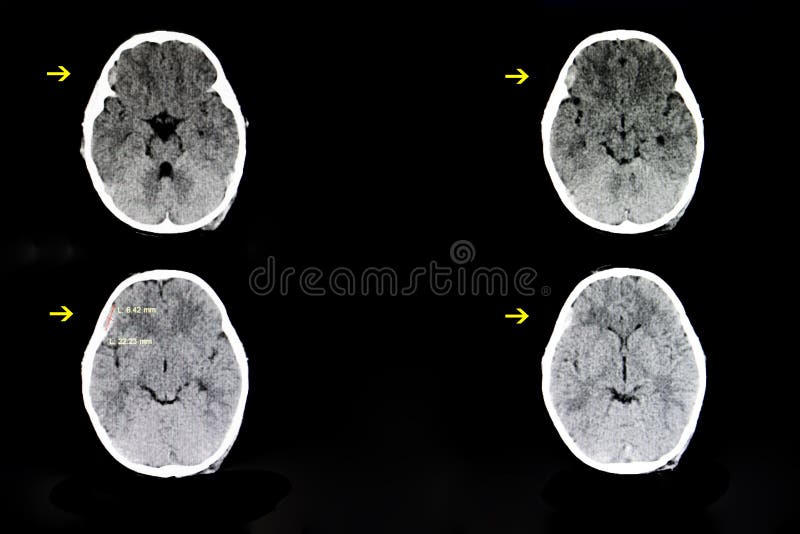

Scansione Tc Della Testa Di Un 77 Anno Vecchio Che Mostra Un Acuto L Ematoma Subdurale Foto Stock Alamy

Testa Di Scansione Tc Con L Ematoma Subdurale Atrofia Foto Stock Alamy

Scansione Tc Del Cervello Che Mostra L Ematoma Subdurale Foto Stock Alamy

Scansione Tc Della Testa Che Mostra Un L Ematoma Subdurale Foto Stock Alamy

Scansione Tc Della Testa Con L Ematoma Subdurale Foto Stock Alamy